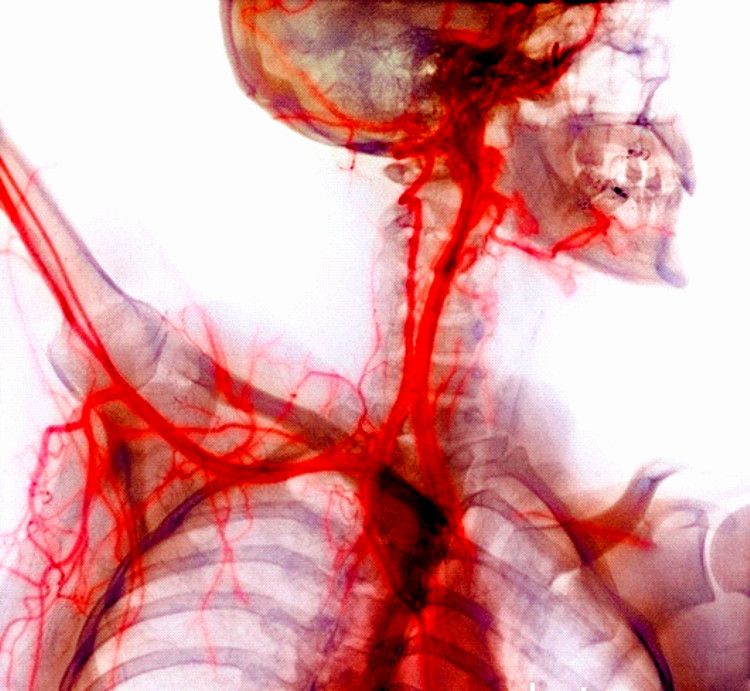

O sistema circulatório é responsável pela defesa do sistema imunológico e pela distribuição de elementos do sangue para os tecidos do corpo, mas para que eles cheguem até lá, o sistema utiliza o coração para bombear o sangue com os nutrientes até o seu destino.

Já o sangue é bombeado pelo coração através das artérias e das veias. As artérias são responsáveis por bombear o sangue para fora do coração, elas tem uma camada mais espessa e são mais resistentes. As veias são responsáveis por bombear o sangue de volta para o coração, seu mecanismo é cheio de válvulas para controlar o sangue corretamente durante toda o seu trajeto.